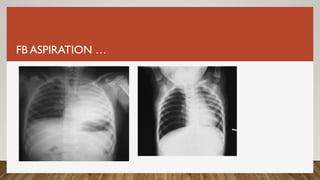

FB ASPIRATION…

FB ASPIRATION

• 20-50% of FBs are diagnosed more than a week after aspiration

• History & physical exam

o CBC

o Plain radiography

o CT scan

o MRI

o Bronchoscopy